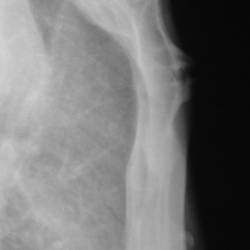

Травма. Пациент направлен на рентгенографию локтевого сустава.